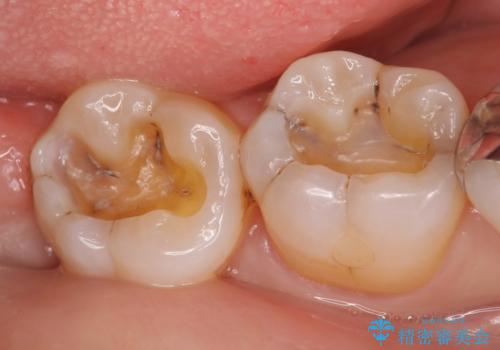

- 右下奥歯の古い銀歯をやり直したいといらっしゃった方の症例です。

銀歯を除去後、セラミックインレーにて修復しました。